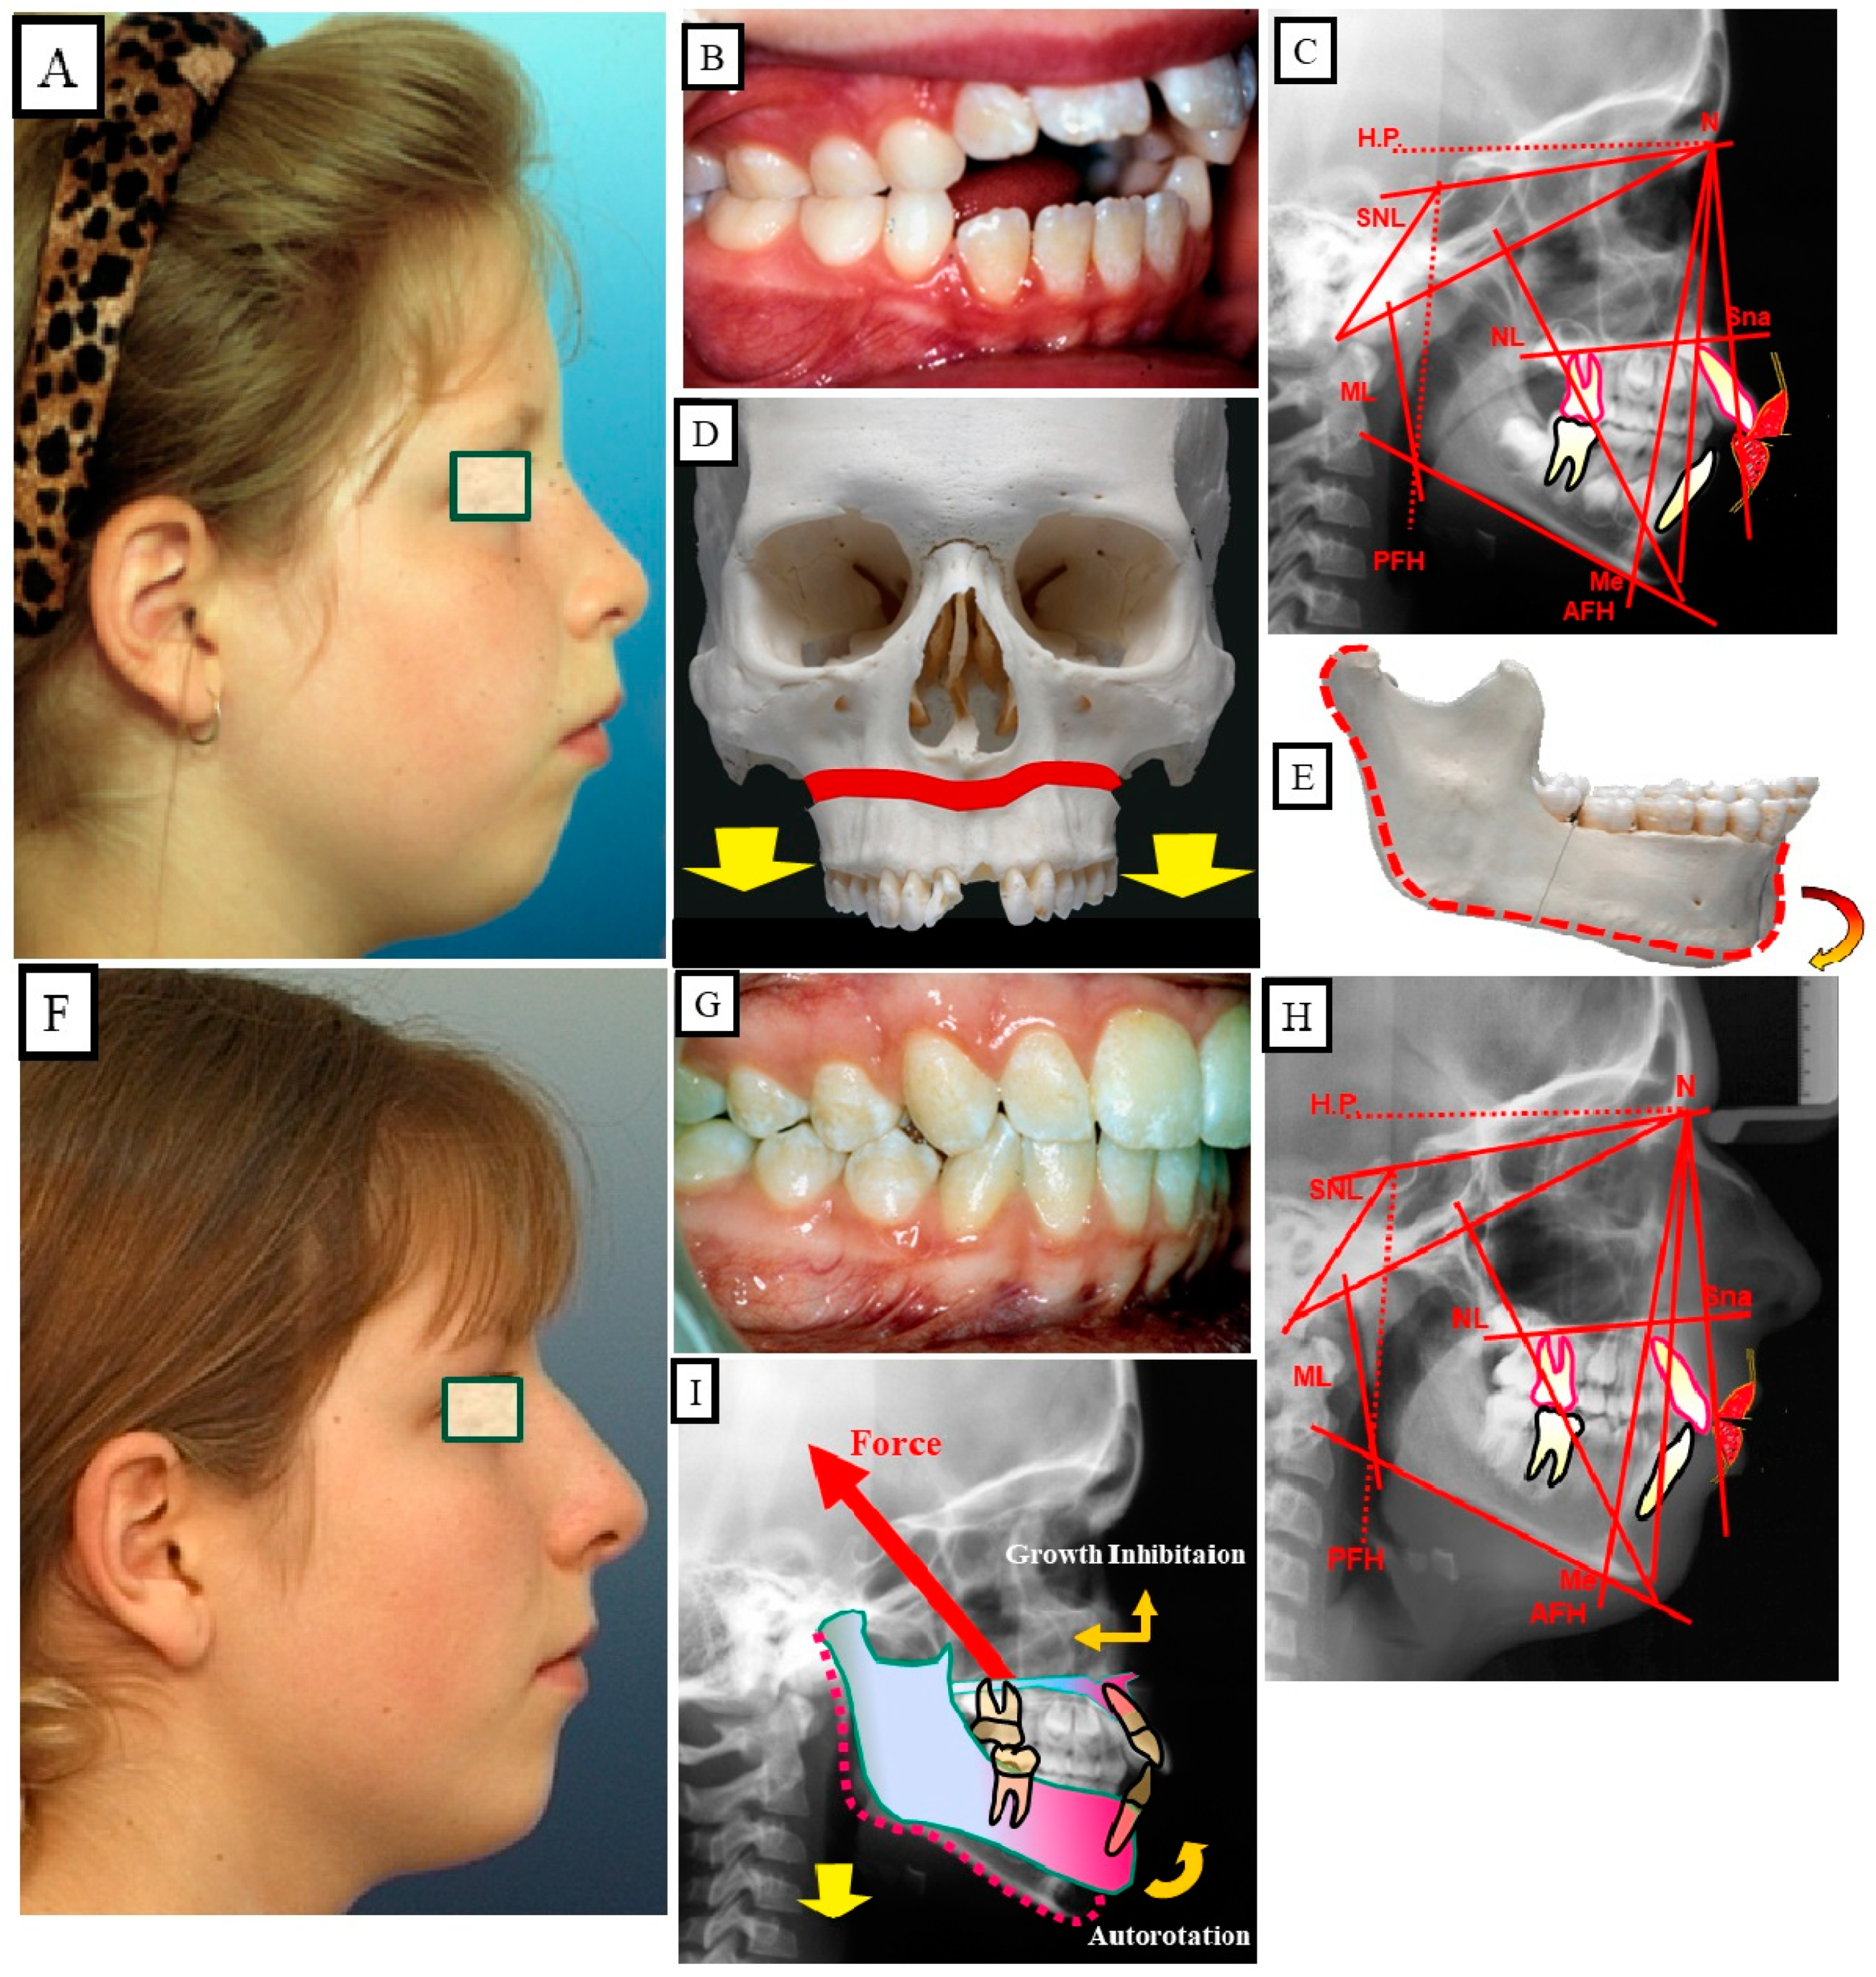

10.2. Skeletal Treatment by Influencing Growth